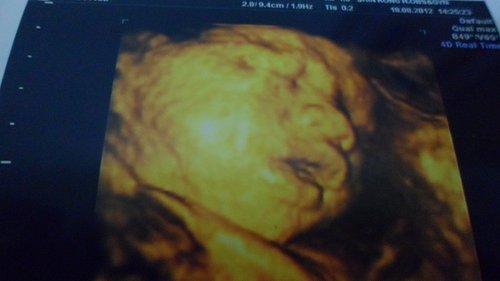

• 31週去照4D超音波

昨天花了二千元照4D超音波(貴)

上次是醫生免費讓我們照的.這次要自費

想說還是再照一次因為很怕小肉彈沒長眼睛

(之前看新聞在美國有小寶寶出生後沒有眼睛所以很擔心)

不過看到小肉彈的臉臉還是和上次28週時差不多